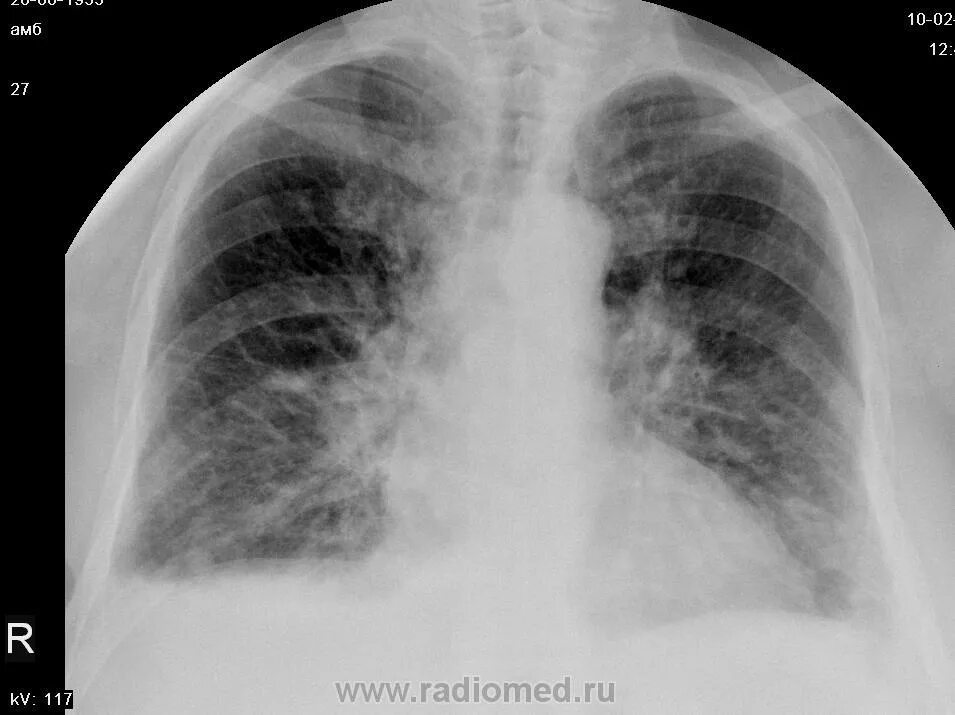

Метастазы плевры